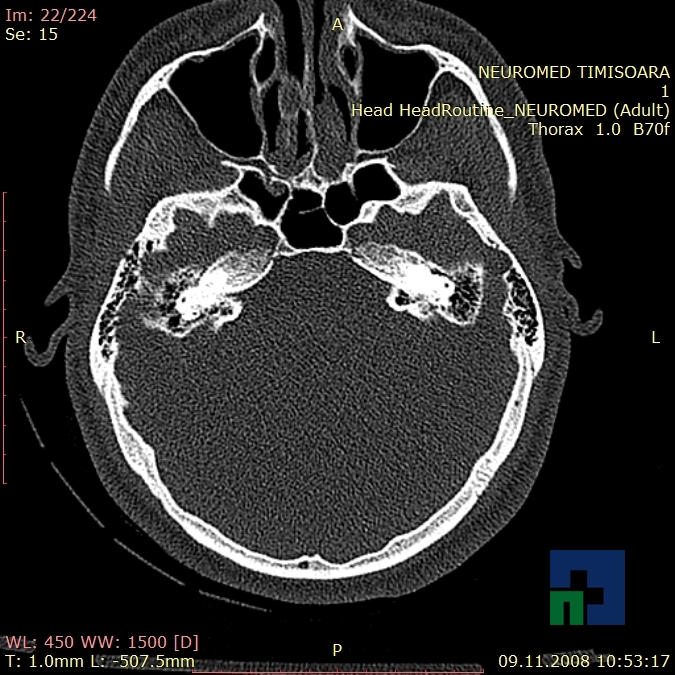

Examinare de rutină cerebrală, nativ și cu substanță de contrast (SDC) pentru diagnosticul:

- Accidentelor vasculare cerebrale ischemice sau hemoragice

- Tumorilor cerebrale

În cazul traumatismelor cranio-cerebrale:

- Evaluarea deplasării liniei mediane

- Evaluarea cisternelor perimezencefalice

- Diagnosticul edemului cerebral, a contuziei cerebrale, a leziunilor axonale difuze edematoase/hemoragice, a dilacerării cerebrale, a hematomului intraparenchimatos posttraumatic, a hematoamelor subdurale/extradurale (acute, subacute, cronice), a hemoragiei intraventriculare, a hemoragiei subarahnoidiene